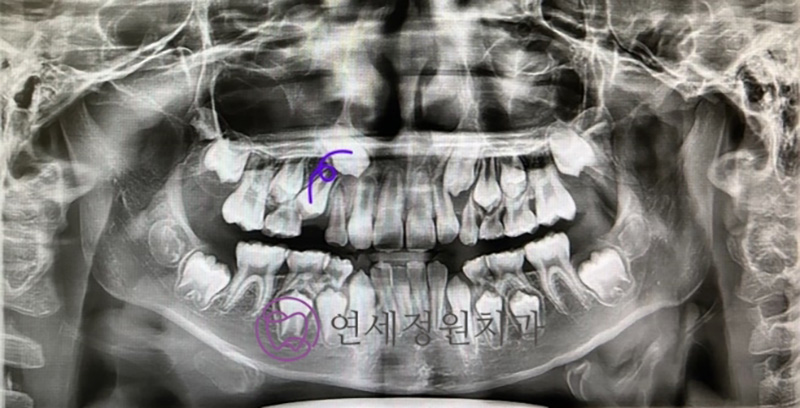

His most recent panoramic image shows the canine now erupting in a much healthier position.